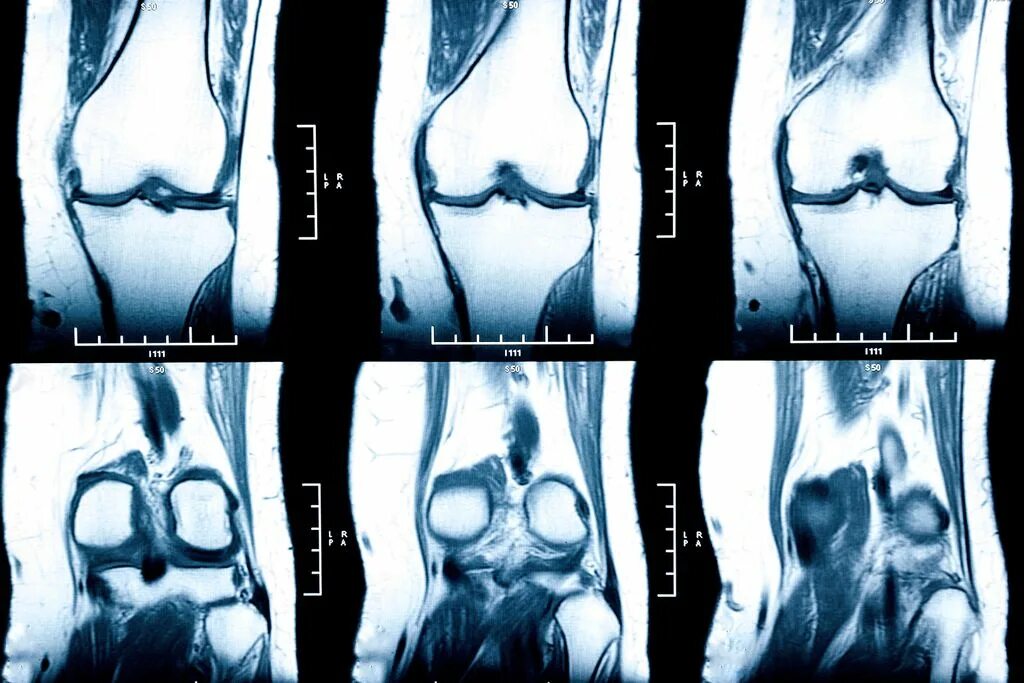

Мрт коленного сустава одежда